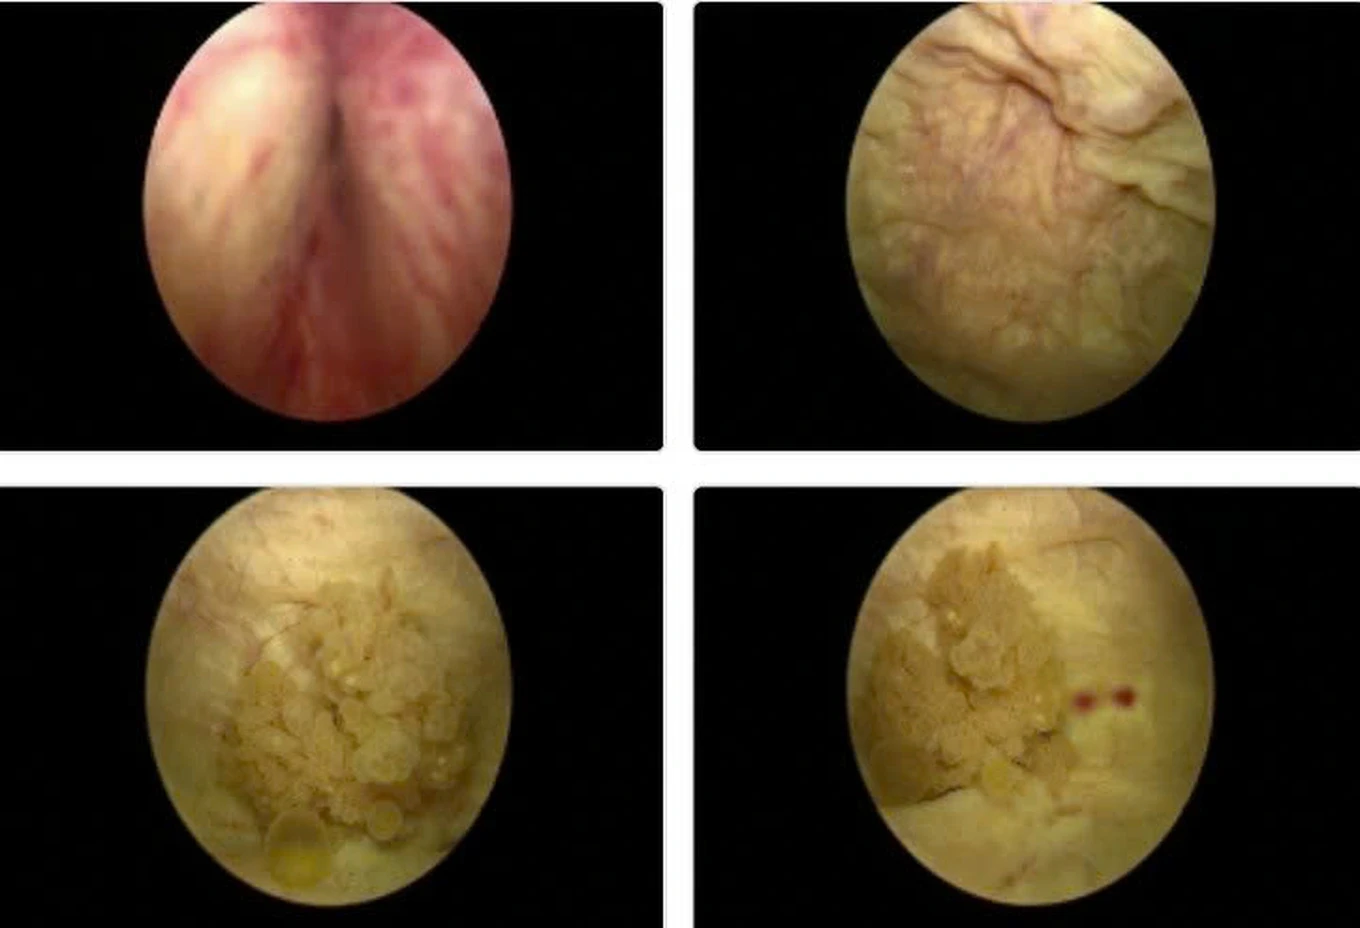

Hình ảnh nội soi u bàng quang vị trí sát lỗ niệu quản trái kích thước 2cm, có chỉ định phẫu thuật nội soi cắt u bàng quang sớm để chẩn đoán tế bào học (Ảnh: Bệnh viện cung cấp).